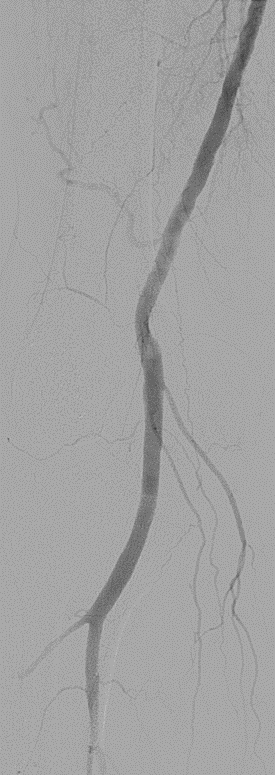

★ Case 5

Female,82 y

Severe claudication over 1 year in both extremities esp. in the left

DM over 10 years

CTA:SFA-PA long CTO

左右滑动查看